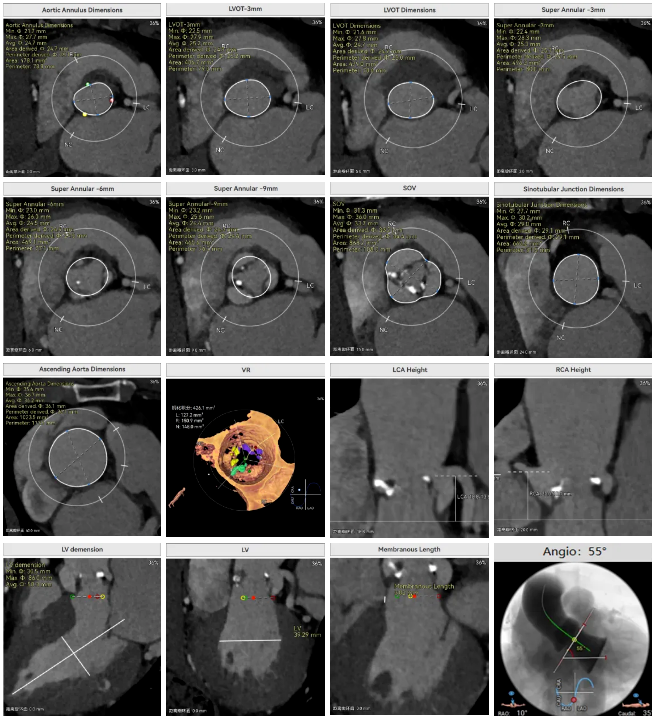

罗建方教授 广东省人民医院(点击查看专家详细简历) 设计本为临床需,耐久守护好芳华:任何医疗产品的设计初衷与最终归宿,都应落在 “临床获益” 这一核心上。尤其在 TAVR 领域,年轻患者预期寿命长,术后瓣膜的长期性能直接关乎其生活质量与生存预后。瓣膜耐久性问题,是落到临床实践中亟待突破的关键课题。传统瓣膜在长期使用中,可能因结构老化、功能退化等问题,难以满足年轻群体数十年的健康需求,二次手术风险也随之攀升。因此,产品设计必须直面这一临床痛点:通过材料革新增强抗钙化性能及生物相容性,以技术突破延长瓣膜有效使用寿命。此次临床应用的预装干瓣Prostyle A®是TAVR领域的革新理念,干瓣预期会为临床提供更耐久性的保障,实现了与临床需求的精准对接,为年轻群体的瓣膜治疗提供更坚实的保障。 李捷教授 广东省人民医院(点击查看专家详细简历) 干瓣技术求革新,性能兼顾护临床:干瓣的技术革新在创新的同时需要和临床实际需求深度耦合,兼顾TAVR术中的核心考量点。临床操作中,瓣膜能否顺利过弓,直接影响手术效率与安全性。Prostyle A®短瓣架设计及第二台阶的柔顺设计,术中操作丝滑;同时,瓣膜植入后的径向支撑力必须平衡得当,才能实现稳定锚定;释放后造影显示:瓣膜形态舒展,轻度瓣周漏,舒张压升高,冠脉开口未受影响;瓣周漏是影响术后效果的关键隐患,双层裙边设计通过多重密封机制降低反流风险,为患者长期获益筑牢防线。这些性能的协同优化,最终目的是让干瓣在临床中真正做到 “好用、耐用、安全用”,为患者预后提升提供坚实支撑。 患者病史 患者因 “活动后气促伴头晕 2 月” 入院。 现病史:2月前无诱因出现活动后气促,休息后缓解,伴头晕,夜间阵发性呼吸困难。超声检查发现:主动脉瓣重度狭窄并重度返流(跨瓣流速 4.3m/s,峰值压差 73mmHg);主动脉 + 冠状动脉 CTA 提示主动脉瓣显著钙化,升主动脉及分支粥样硬化,冠状动脉轻度狭窄(RCA 狭窄 30-40%)。 既往史:高血压病史 15 年,规律服药,血压控制稳定。 术前诊断:非风湿性主动脉瓣狭窄伴关闭不全(重度)、心功能 II 级(NYHA)、高血压病 2 级(高危)、冠状动脉粥样硬化。 术前CT 三叶瓣,瓣叶增厚中度钙化,右无交界钙化粘连,瓣环径25.1mm,LVOT 25.1mm,直筒型结构;窦部空间足够,升主未见增宽,瓣环水平夹角55°;冠脉开口位置佳,无冠脉风险;入路散在钙化、外周双侧入路无明显迂曲,双侧内径可、中分叉,左右侧均能够支持20F 大鞘通过。 造影角度及入路 右窦居中位RAO 5° CAU 26° 左冠切线位LAO 11° CRA 12° 手术策略 右侧股动脉为主入路,左侧为辅助入路;使用20球囊预扩,准备AV26瓣膜,冲洗口朝向3点钟方向送入输送系统性能,初始定位真实瓣环0位释放,最终锚定约瓣下3mm,工作位评估瓣膜稳定性与冠脉情况。 手术过程 根部造影 20mm 球囊预扩无明显腰征 术中使用26号瓣膜,瓣膜释放贴边迅速 80% 工作位观察瓣膜位置良好 释放后造影显示:瓣膜形态舒展,轻度瓣周漏,舒张压由术前30mmHg升为 60mmHg,冠脉开口未受影响。 术后超声:跨瓣流速降至1.6m/s,平均压差降至5 mmHg,心功能显著改善。 Prostyle A®预装干瓣——助力临床最优化解决方案: 1. 抗钙化与耐久性:Micro-EX™专利技术提升瓣膜抗钙化能力,适配患者瓣叶中度钙化的解剖特点,为长期疗效提供保障。 2. 柔顺过弓与精准定位:短瓣架设计 + 远端超滑涂层,确保患者输送系统过弓顺畅;瓣架流入端微直筒设计,让定位贴边更迅速,减少了手术时间; 3. 80% 可回收设计:便于术中调整观察,减少起搏时间,从而减少并发症。 4. 简化手术流程:预装设计缩短操作时间,20F 大鞘兼容外周入路,降低血管损伤风险。